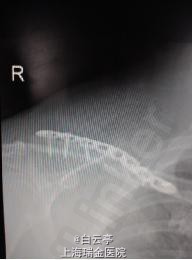

诊断:右侧锁骨中段骨折。 治疗:切开复位内固定术。

随访:一月后患者骨折愈合,肩关节活动可。 讨论:锁骨解剖钢板应尽量置于锁骨上方。